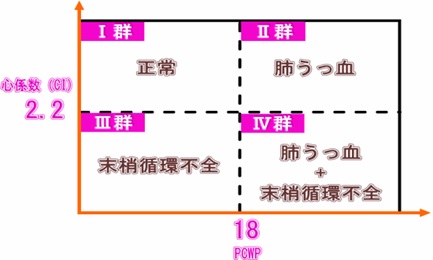

そこでフォレスター(Forrester)分類

フォレスター分類とは、心係数と肺動脈楔入圧の

2つの定量的・客観的データに基づいて心不全の程度を分類するものです。

このうち心係数は心臓超音波検査で容易に計測できますが、

肺動脈楔入圧はスワン‐ガンツという心臓カテーテルを用います。

超音波検査は、患者さんに苦痛を与えず、繰り返して検査できるので、

実際の現場の臨床では、心係数の確認が重要です。

カテーテル検査が実施できない日常の外来診療においても、

この係数だけで、末梢循環不全の有無を鑑別できることができます。

心係数2.2以であれば末梢循環不全のないⅠ群【死亡率3%】もしくはⅡ群【死亡率9%】、

心係数2.2未満であれば末梢循環不全でⅢ群【死亡率23%】もしくはⅣ群【死亡率51%】です。

M.Yさんの心臓超音波検査で得られた心係数は2.76でした。

2.76>2.2ですから、M.Yさんは末梢循環不全を伴わないⅠ群もしくはⅡ群です。

ただし、Ⅰ群は心機能正常群ですから、明らかな心不全であるM.YさんはⅡ群、

すなわち、末梢循環不全を伴わない肺うっ血タイプの心不全(うっ血性心不全)であることが推定されます。

客観的な評価尺度である超音波検査による心係数計測により、

フォレスター分類に当てはめると末梢循環不全を伴わない

Ⅰ群もしくはⅡ群に相当しました。

フォレスター分類Ⅱ群の末梢循環不全を伴わない肺うっ血タイプの左心不全と評価することができました。

フォレスター分類は心不全の治療方針の決定に有用です。

Ⅱ群の心不全の場合、治療の基本戦略は前負荷の軽減です。